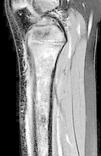

Presentamos el caso de una niña de 6 años con cojera y dolor tibial progresivo de 10 días de evolución, sin fiebre o antecedente traumático. Tanto la paciente como su madre habían sido diagnosticadas previamente de hemoglobinopatía C heterocigota; y su padre estaba diagnosticado de rasgo drepanocítico. La paciente refería haber presentado varios episodios de dolor óseo en distintas localizaciones de miembros superiores e inferiores durante el último año. La exploración física reveló dolor a punta de dedo en la metáfisis proximal de la tibia derecha, sin otros hallazgos significativos. La analítica mostró niveles aumentados de proteína C-reactiva (7,9mg/dl), lactato-deshidrogenasa (420mg/dl) y bilirrubina (1,4mg/dl), sin alteraciones en el hemograma, la coagulación o el resto de parámetros de la bioquímica. Los hallazgos de la radiografía simple fueron normales, por lo que se realizó gammagrafía ósea ante la sospecha de osteomielitis crónica no bacteriana en base a los antecedentes de dolor musculoesquelético de repetición. Ante la captación patológica del trazador exclusivamente a nivel de metáfisis tibial, se indicó una resonancia magnética, que evidenció un infarto óseo agudo de gran tamaño (figs. 1-2). Este hallazgo condujo a la repetición de la electroforesis de hemoglobinas, que detectó un 46% de hemoglobina S y un 44,5% de hemoglobina C, confirmándose así el diagnóstico de hemoglobinopatía SC.